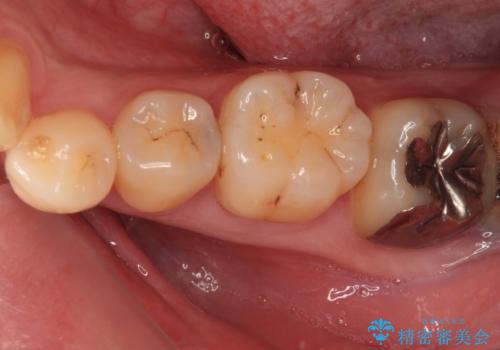

その他は銀歯のインレー(部分的な詰め物)が装着されており、それらはむし歯を除去した後にセラミックインレーにて修復治療を行い、左下と根管治療を行う左上の奥歯はオールセラミッククラウンにて補綴治療を行うこととしました。

根管治療の途中で、矯正治療の後戻りが気になるとのことで、下顎前歯の叢生を改善するためにマウスピース矯正を並行して行いました。

目立っていた銀歯がなくなり、患者様には大変満足していただけました。